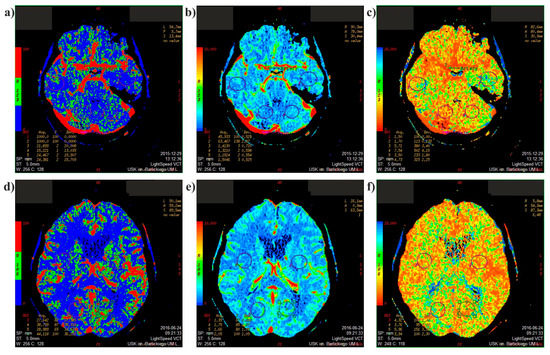

2.1. Medical Data